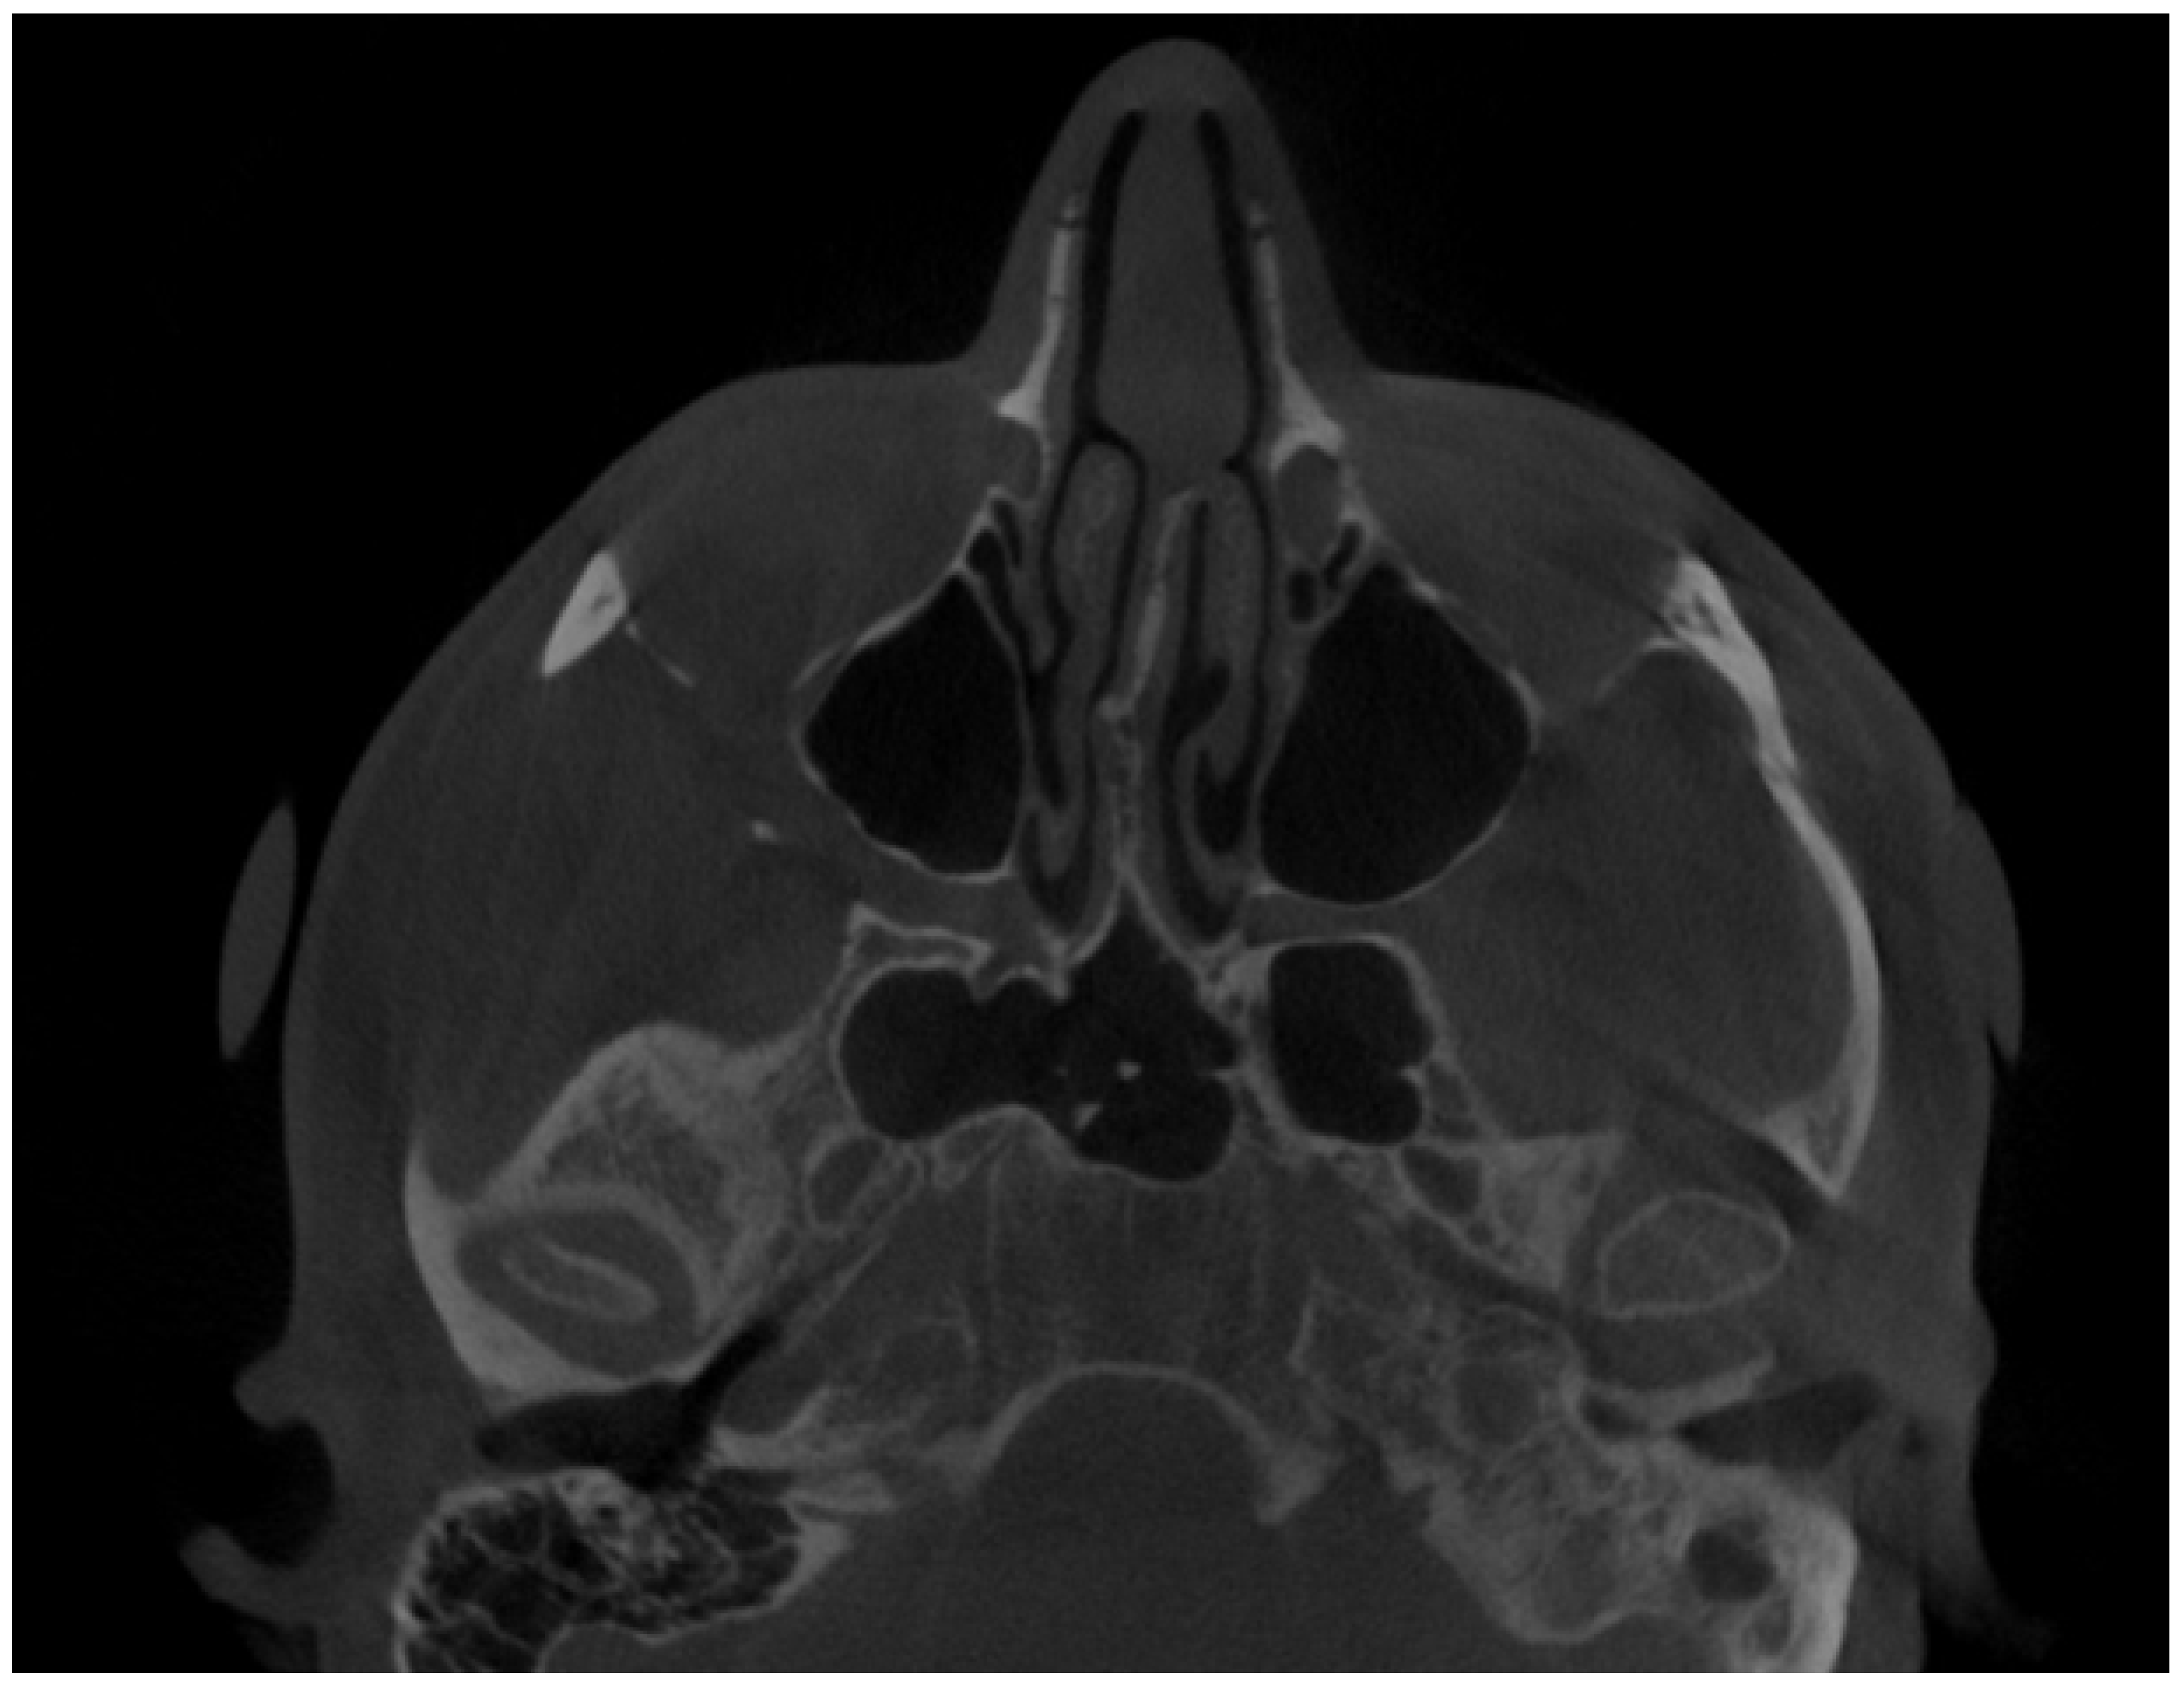

CBCT axial view—enlargement of the left mandibular condylar head. Atypical osteophytes or bone irregularities can have different shapes and sizes while the condylar head is evaluated. The condylar head might have a different shape, size, and contour compared to the opposite healthy side.